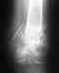

Не сочтите за недоверие, но с данными МРТ и снимками рентгена были ознакомлены ещё несколько ведущих врачей Екатеринбурских и Нижнетагильских больниц. И все они склоняются к мнению, что операция в моём случае не является необходимостью.

Безусловно, перелом позвонка срастется без лечения. Проблемой является нарушение его формы, что приводит к изменению формы позвоночника. Отсутствие боли через месяц после травмы - это хорошо, но ни о чем судить не позволяет.